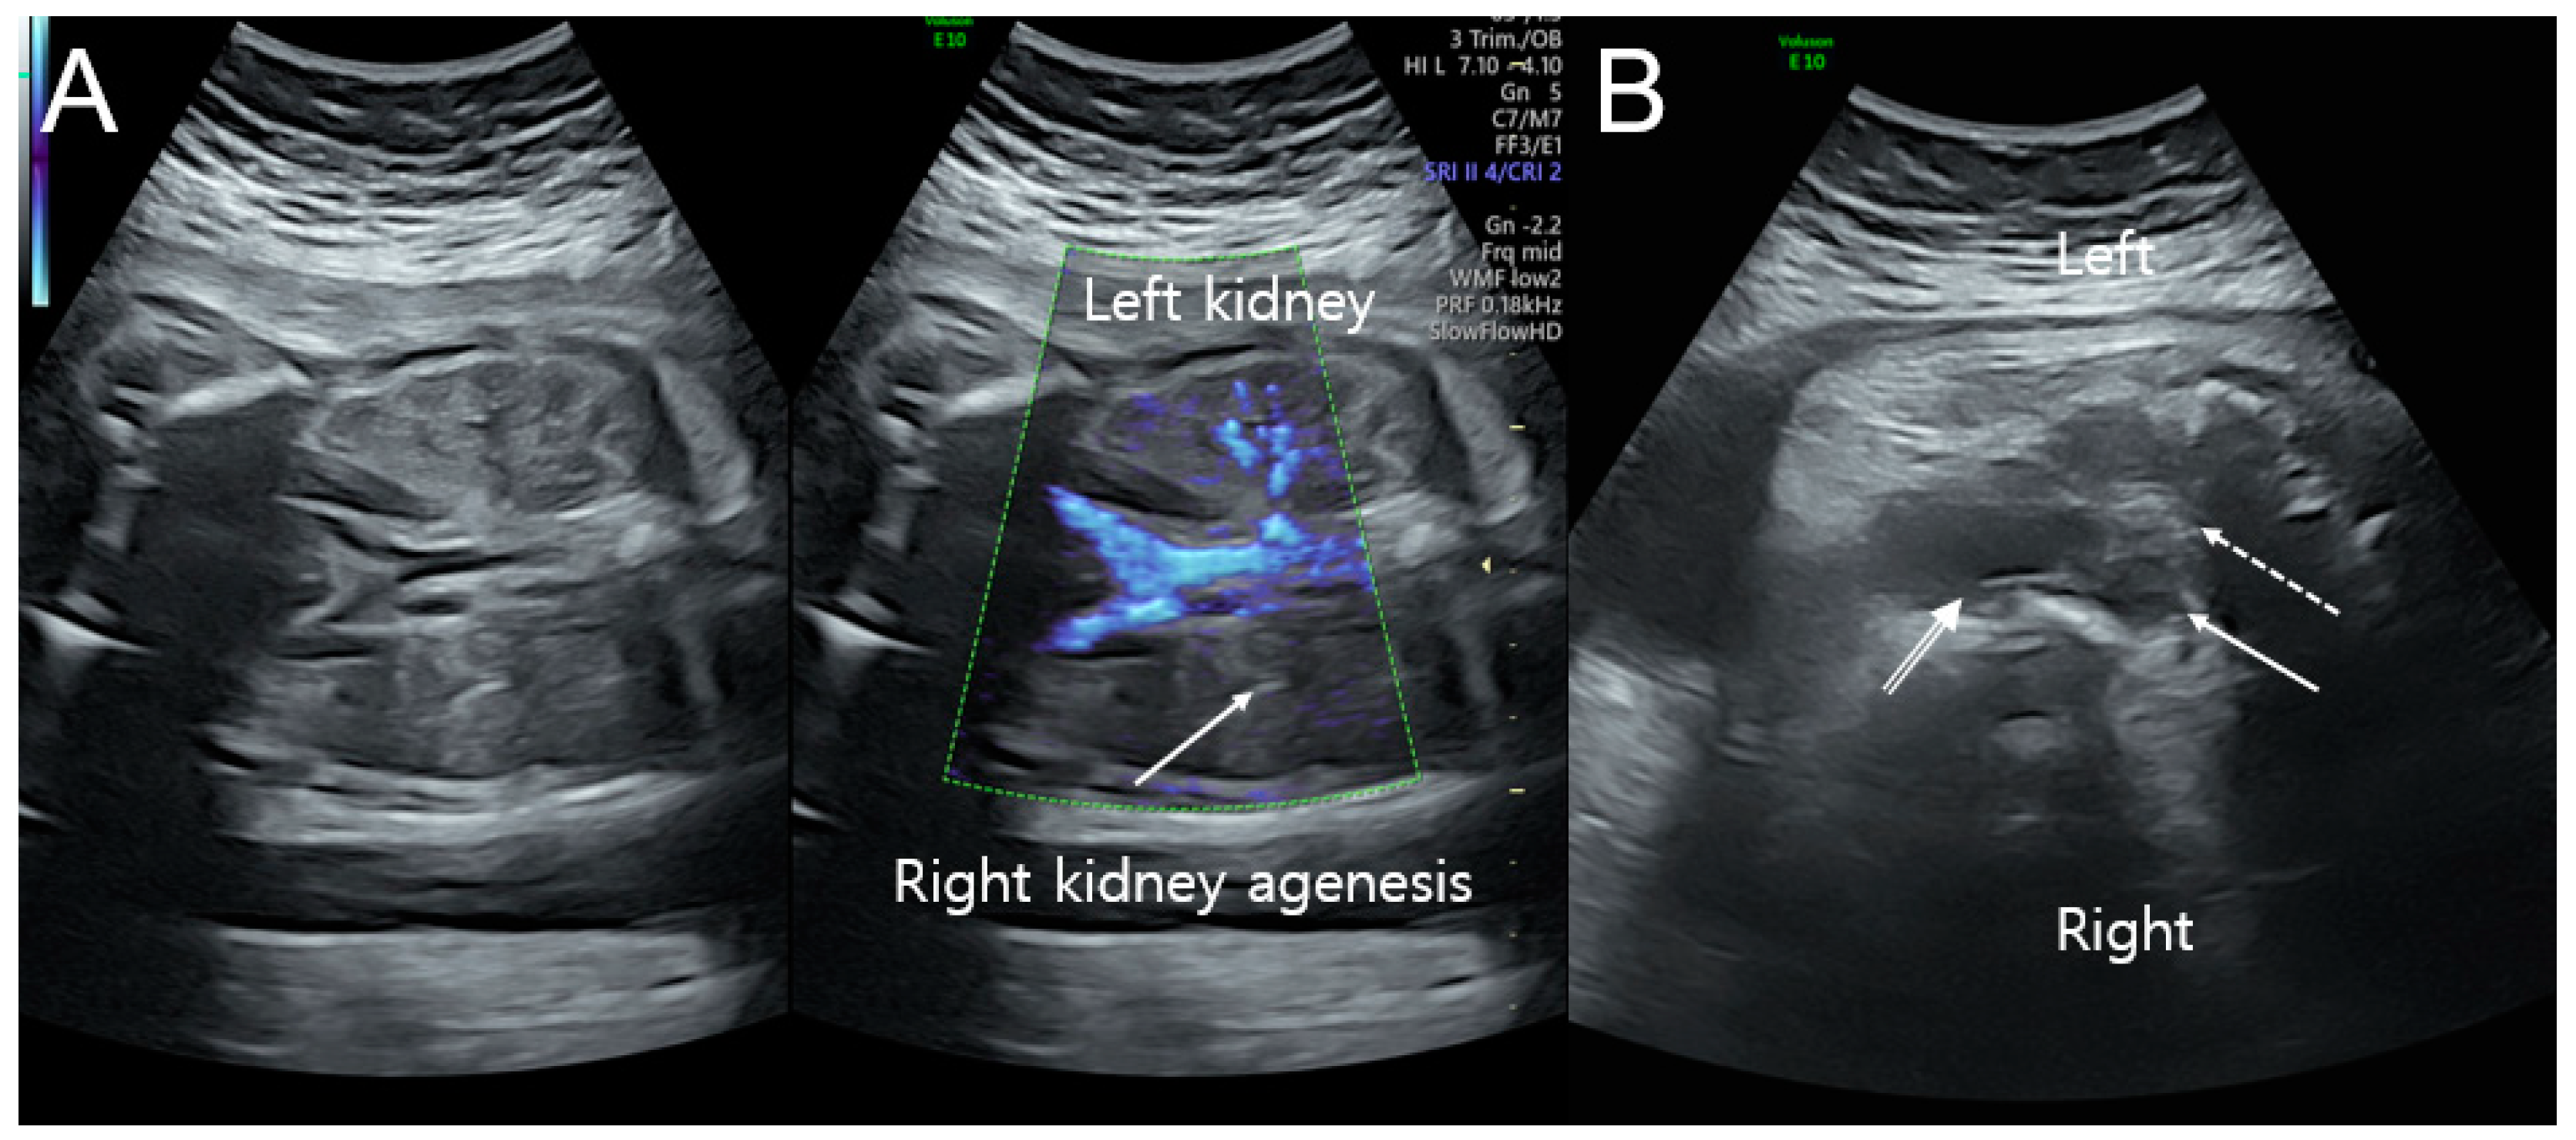

A transabdominal ultrasound scan showed a normally growing female fetus with right kidney agenesis. On a transabdominal ultrasound scan, the estimated fetal weight and abdominal circumference were consistent with 32 weeks of gestation, with adequate amniotic fluid and no placental abnormalities observed. The fetal brain and heart were normal, and Doppler waveforms from the umbilical artery and middle cerebral artery were within acceptable ranges. Additionally, detailed ultrasonographic examinations using 2D and Doppler ultrasounds revealed right kidney agenesis, uterine didelphys, hydrocolpometra, and a vaginal cyst (Figure 1A,B). Based on the imaging, fetal OHVIRA syndrome was highly suspected.

Figure 1.

Ultrasonographic findings at prenatal examination. (A) Color Doppler ultrasound of the left kidney with the renal artery and right kidney agenesis (arrow) without the renal artery at 32 weeks of gestation. (B) Uterine didelphys with right hydrocolpometra (arrow), left uterus (dotted arrow), and vaginal cyst (double-lined arrow) at 37 weeks of gestation.